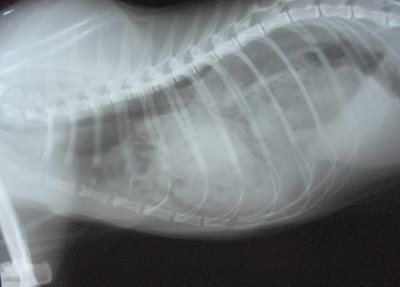

We x-rayed him and quickly found out what was going on. We confirmed that his tail was fractured and dislocated. However, what was more remarkable on the x-ray was the lack of intestines, stomach and liver. The abdomen looked quite empty! Where did they go? We then x-rayed the chest and found the missing organs. No wonder he was not feeling well.

How did this happen? We assumed that when Bill Murray went missing he sustained a significant injury like a fall from a great height OR being struck by a car. This caused his diaphragm (the muscle separating the chest and the abdomen) to have a tear or hole in it. The organs in the abdomen migrated up through this hole and crowded his chest cavity! It was amazing that he was still able to breathe, eat and walk around!